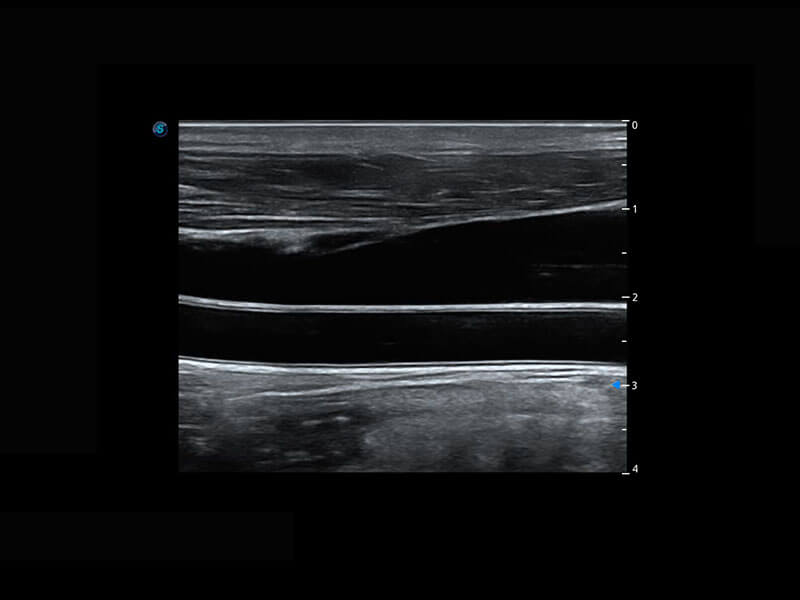

P60搭載寬頻帶線陣探頭、寬景成像、彈性成像技術(shù),為您提供乳腺應(yīng)用方案。P60支持高頻相控陣探頭、線陣探頭、腹部高頻探頭、腹部微凸探頭等,豐富的探頭群搭載敏感的彩色血流成像,適用于新生兒多種臟器檢測(cè)要求,滿足新生兒篩查需求。

新生兒脊髓圓錐